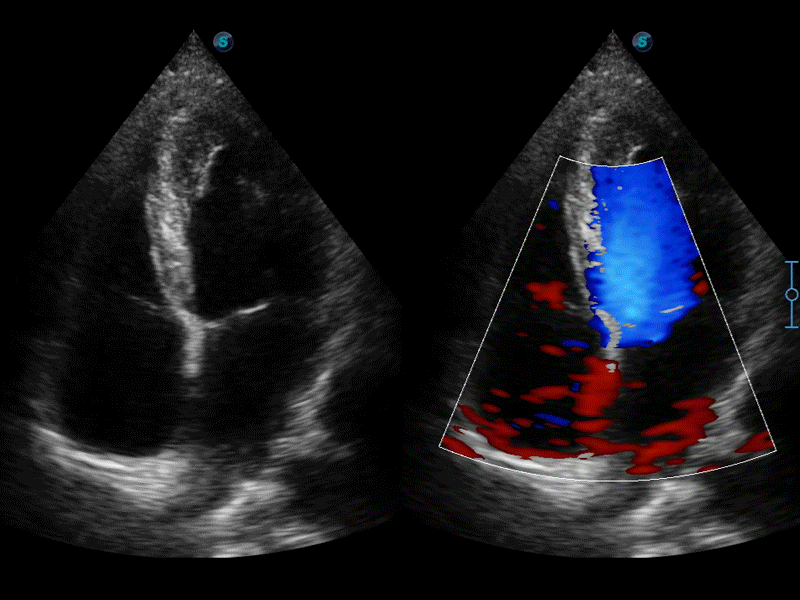

自動(dòng)識(shí)別前后壁內(nèi)膜厚度,為心血管疾病早期評(píng)估提供快速準(zhǔn)確依據(jù)。

自動(dòng)識(shí)別收縮和舒張末期心肌內(nèi)膜,自動(dòng)計(jì)算射血分?jǐn)?shù)EF值。